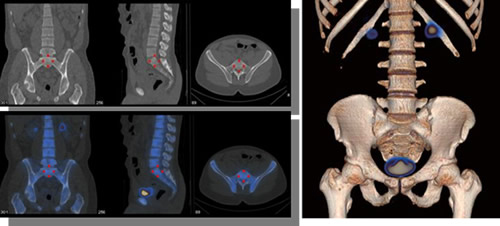

臨床的には、がんの骨転移や軟部腫瘍、心疾患などのより詳しい診断、ならびにこれまで呼吸による影響を受けやすかった胸腹部の診断に貢献することを目指しています(下図参照)。

Optima NM/CT 640の撮影画像(実効線量: 1.13mSv)

▲Courtesy of Dr. Ph. Declerck, Clinic Saint Jean, Belgium

重ね合わせ画像は核医学データ処理装置「GENIE-Xeleris」(薬事承認番号:20700BZY00161000)にて実施